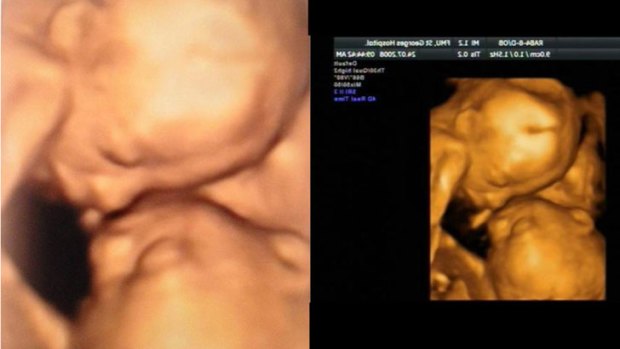

The difference between sonogram. In this article we will discuss in detail the tips and signs about how to spot a fake ultrasound. If you dont see the baby in a scan it doesnt necessarily mean that its not there.

Heres how you can tell if an ultrasound photo isnt the real thing. You can not tell the sex of your baby until you are 20 weeks. It is much better if you scan it to see the full details of the imagethats if you really want to go the extra mile.

15 weeks 5 days ultrasound baby boy pinterest. 10 Mar 2022 One of the ways by which a person can spot fake ultrasound pictures is through Google image search. They are the only.